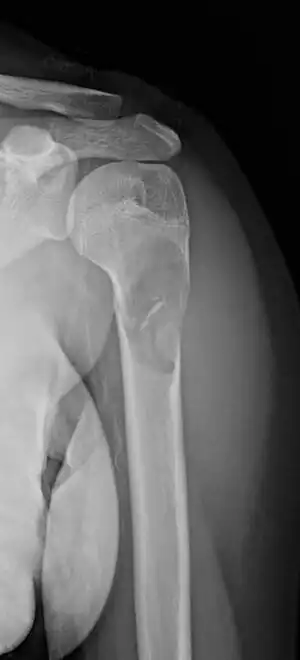

MRI showing simple bone cyst of left upper thigh bone near hip.

Magnetic resonance imaging (MRI) is used to identify the precise location of the cyst, to see how aggressive the disease is, and to determine the actual shape and size.[4] The MRI uses a combination of magnets and radio-frequencies to produce various detailed, computerized images of the cyst and its surrounding body structures.[4]

Most simple bone cysts do not cause any symptoms and are discovered as accidental findings on radiographs or CT scans made for other reasons.[3] Although it can form in any bone structure, it is predominantly found in the long bone of the upper arm near the shoulder, and long bone of the thigh near the hip.[6] Large lesions can cause nearby areas of bone to thin, which may result in a fracture and cause pain.[1][2] There may be a swelling or problem in moving the affected bone.[1]

Simple bone cysts are often found incidentally on X-rays. About 90 to 95% of the lesion is found in metaphysics of long bones. The cyst is centered, oblong in shape along the long axis of a long bone. Rarely, they are large and multicameral and are found in diaphysis. When fracture is present, there may be a small bone fragment migrated in the cystic fluid. This is called "fallen fragment sign" which is diagnostic of simple bone cyst. Besides, a bubble migrating upwards (known as "rising bubble sign") is another feature suggesting of simple bone cyst.[7]